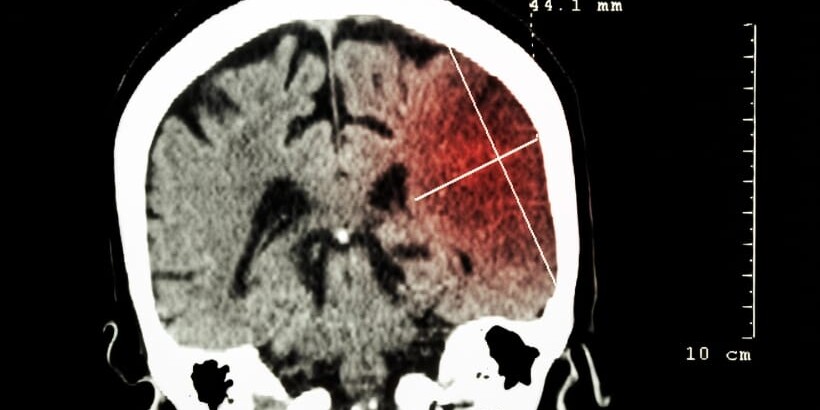

Treatment of Brain Hemorrhage: Causes, Symptoms & Options

A brain hemorrhage can be a frightening term — and rightly so. When bleeding occurs in or around…